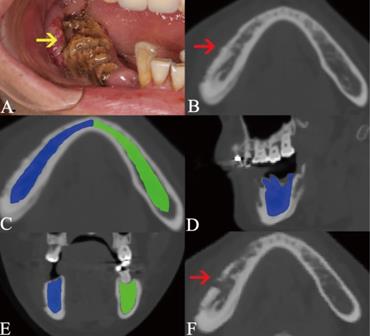

Figure 5

The recurrence of post-surgical lesion. Red arrow points out the pre-surgical MRONJ lesion (A). Image B shows the lesion after surgery. Yellow arrow indicates the recurrence of post-surgical lesion (C). The segmentation of cancellous bone nearby post-surgical lesion is colored as blue, while the same area in the bilateral side is segmented as the control and colored as green (D).

41 patients had been performed with surgery and 16 patients were recurred after surgery. Of 16 recurrences, 13 occurred in the patients receiving sequestrectomy and 3 were found in the patients receiving block resection of necrotic bone. In 41 patients, the average radiodensity values were 888.03. The average ratio 1 was 1.90, and the average ratio 2 was 2.80 (Figure 7). The recurrence group showed significantly greater radiodensity values (P=0.025), ratio 1 (P=0.029) and ratio 2 (P=0.026) than the non-recurrence.

Our study demostrated that the radiodensity values of the surrouding of post-surgical lesions in patients with recurrence were absolutely and relatively higher than those patients without recurrence. It would be clinically useful to alert the clinician of an increased risk of recurrence if the radiodensity values around the post-surgical lesions are abnormally high. Takaishi et al. [31] also reported that a rise of alveolar bone mineral density occurred near the necrotic lesion of MRONJ, which suggested a tendency of new MRONJ onset.